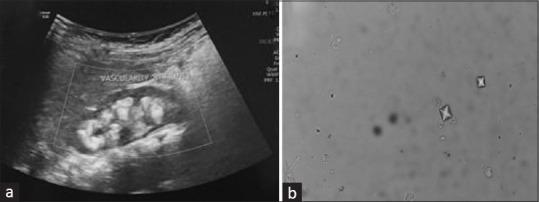

Hypercalcemia in infants presents with a variety of clinical features and the etiology of hypercalcemia varies with age. Here we present a case of hypercalcemia in an infant presenting with nephrocalcinosis and nephrolithiasis. Our investigations led us to a diagnosis of primary hyperoxaluria (PH) type 2, a rare metabolic disorder, along with hypercalcemia, a never before reported association. A 9-month-old female presented with urinary tract infection and systemic features requiring hospitalization and parenteral antibiotics. Investigations revealed bilateral medullary nephrocalcinosis. Genetic testing revealed a diagnosis of Primary hyperoxaluria type 2 with two possible mutations. Sanger sequencing of the parents identified the pathogenic mutation in the mother. This is the first report of a genetically proven case of primary hyperoxaluria type 2 associated with hypercalcemia.